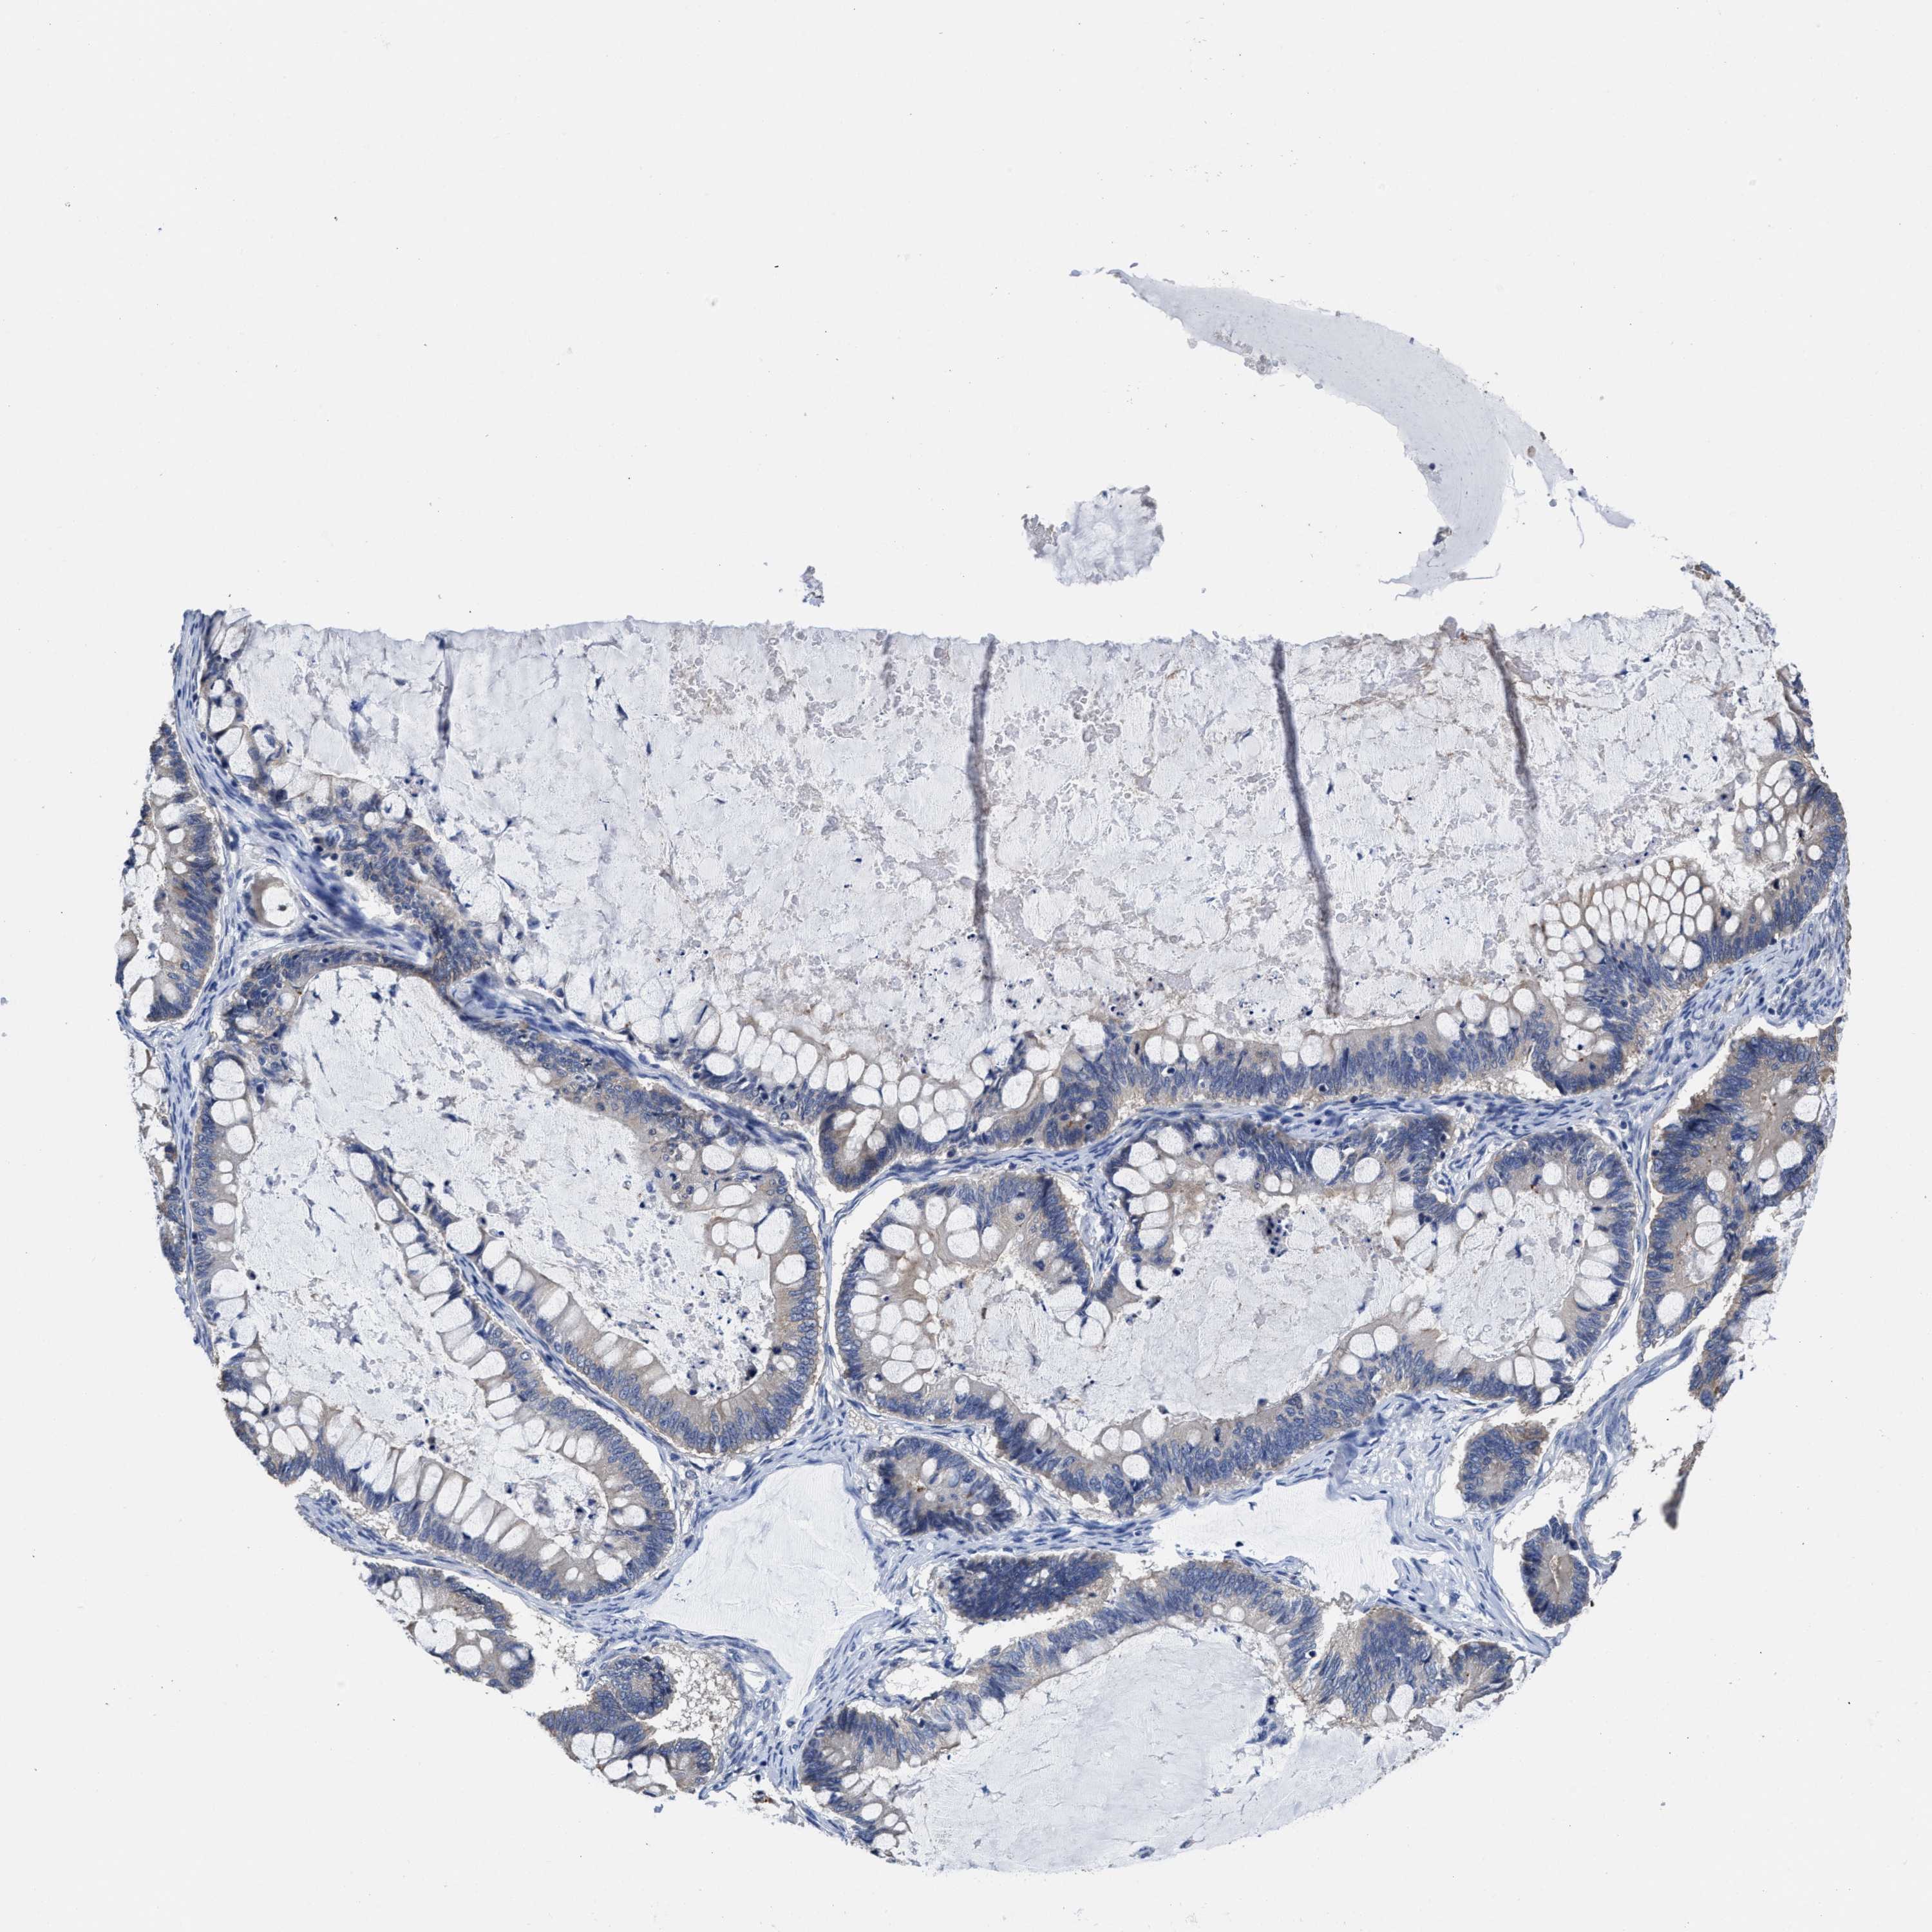

OVARIAN CANCER - Protein expressioni

A mouse-over function shows sample information and annotation data. Click on an image to view it in a full screen mode. Samples can be filtered based on level of antibody staining by selecting one or several of the following categories: high, medium, low and not detected. The assay and annotation is described here.

Note that samples used for immunohistochemistry by the Human Protein Atlas do not correspond to samples in the TCGA dataset.

Antibody stainingi

Antibody staining in the annotated cell types in the current human tissue is reported as not detected, low, medium, or high, based on conventional immunohistochemistry profiling in selected tissues. This score is based on the combination of the staining intensity and fraction of stained cells.

Each image is clickable and will lead to virtual microscopy that enables deeper exploration of all samples and also displays staining intensity scores, fraction scores and subcellular localization as well as patient and tissue information for each sample.

Antibody HPA018537

Antibody HPA018820

Cystadenocarcinoma, serous, NOS

Carcinoma, endometroid

Cystadenocarcinoma, mucinous, NOS

Carcinoma, NOS